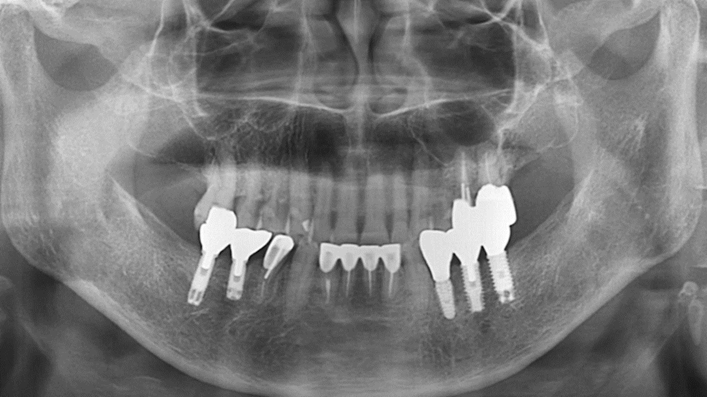

Clinical case: Extraction, immediate placement & loading using

R2GATE solution in aesthetic zone

- Courtesy of Dr. Jong-Cheol Kim, Korea-

Dr. Jong Cheol Kim, immediate loading, digital guided surgery, Digital ONE-DAY Implant, maxillary anterior, #21, guided surgery, immediate loading, AnyRidge, R2GATE, Mega ISQ, MEG Torq, R2GATE Full Surgical Kit

AnyRidge implant system, R2 Guide, R2GATE Full Surgical Kit, Mega ISQ